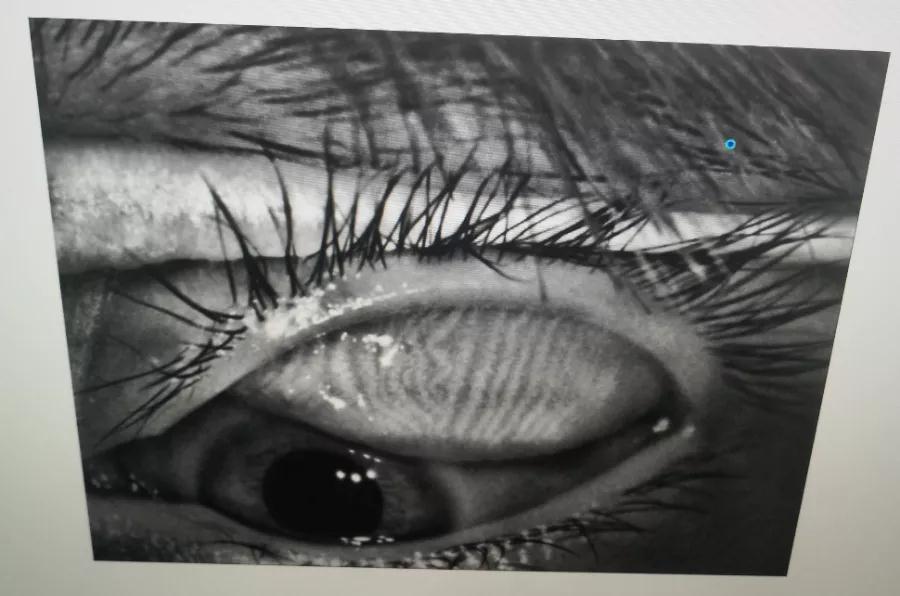

瞼板腺是排列在我們上下眼皮里面,分泌油脂的腺體,這些油脂是組成淚液的重要成分,可以讓淚水更長時(shí)間的停留在眼球表面。瞼板腺油脂減少,淚水蒸發(fā)就會加快,眼球暴露在外的時(shí)間變長,會加重眼睛干澀,時(shí)間一久,干眼也就隨之而來。

通過熱敷并按摩擠壓上下眼瞼,將瞼板腺內(nèi)不能自行排出的分泌物推出,疏通堵塞的瞼板腺開口。

熱敷可以促進(jìn)眼周部位的血液循環(huán),瞼板腺按摩能有效改善瞼板腺功能,解決絕大多數(shù)干眼患者油脂分泌不足問題。

通過強(qiáng)脈沖光高溫消除蠕形螨蟲,同時(shí)脈沖光產(chǎn)生的熱量可以熔解軟化瞼酯,改善瞼板腺內(nèi)脂質(zhì)分泌物的流動性,疏通瞼板腺,提高淚膜的穩(wěn)定性,恢復(fù)正常眼表功能和眼部“鎖水”能力,從病因上治療干眼。